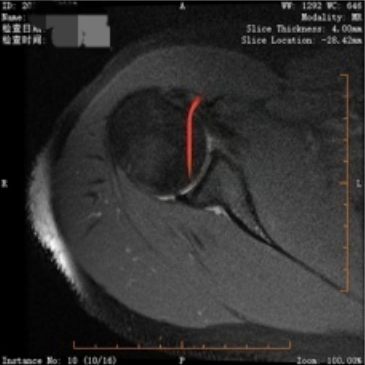

经朋友推荐,小欧来到该院骨二科就诊。通过详细查体及三维CT、核磁共振评估,医生明确诊断其合并Bankart损伤(肩关节盂唇前下方撕裂)和Hill-Sachs损伤(肱骨头后外侧骨折)——这正是导致肩膀反复“出走”的根源。

【撕裂的孟唇】